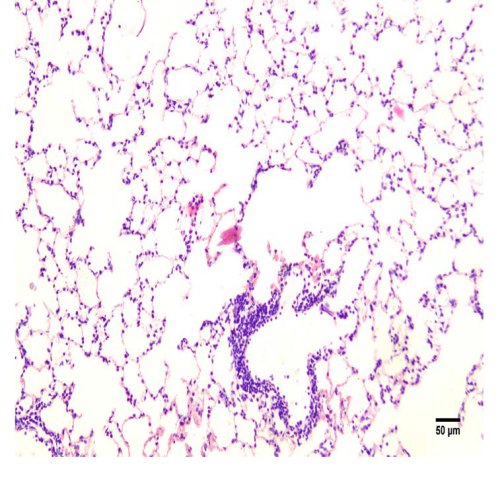

ArticleViewAbstractPharmacognosy Journal,2025,17,5,566-576.DOI:10.5530/pj.2025.17.70Published:September 2025Type:Original ArticleAcute Toxicity Study of the Crude Aqueous Extract of Tribulus terrestris Dried Fruit with Potential Diuretic EffectAmruth Kiran, Praveen Kumar S E, Tatiyana Mandal, K Ganesh Shenoy, Vasudev R Pai, Swati Sharma, and Arul Amuthan Amruth Kiran1, Praveen Kumar S E2, Tatiyana Mandal1, K Ganesh Shenoy1, Vasudev R Pai3, Swati Sharma4, Arul Amuthan1,5,* 1Division of Pharmacology, Department of Basic Medical Sciences, Manipal Academy of Higher Education, Manipal, India 2Department of Pharmacology, Manipal Tata Medical College, Manipal Academy of Higher Education, Manipal, INDIA 3Department of Pharmacognosy, Manipal College of Pharmaceutical Sciences, Manipal Academy of Higher Education, Manipal, INDIA 4Department of Pathology, Kasturba Medical College, Manipal Academy of Higher Education, Manipal, INDIA 5Division of Siddha, Centre for Integrative Medicine and Research (CIMR), Manipal Academy of Higher Education, Manipal, India Abstract:Introduction: Tribulus terrestris is an important medicinal plant used in Indian traditional medicine, the crude aqueous extract of the plant is primarily used to induce diuresis for treating cardiovascular diseases and managing renal stones, etc... The safe dose and adverse effect profile of the extract was not explored adequately in preclinical studies. Hence, the present study was undertaken. Methods: The acute toxicity was assessed based on the OECD guideline number 425: Acute Oral Toxicity – Up-and-Down-Procedure. A total of 11 animals were used in the study. Initially, one animal was administered with a dosage of 2000 mg/kg; and as the animal survived, four more animals were dosed and were observed for survival and other possible adverse drug reactions. The animals' body weight was measured before experimenting and at the end of the study. Biochemical and haematological examinations were done on normal control and test groups. Animals from the test group were sacrificed, and histopathological examinations of the vital organs were carried out. Results: No signs of toxicity or changes in the behaviour were observed in the treatment group. As all the animals survived, it was decided that the LD50 was greater than 2000 mg/kg. However, the changes observed with platelets, total cholesterol and LDL were within the normal limits. Histological examination of the vital organs did not reveal any changes in the architecture of the organs. Conclusion: Our study demonstrated that the crude aqueous extract of Tribulus terrestris dried fruit does not cause toxicity under the 2000 mg/kg dose limit. Keywords:acute toxicity study, crude aqueous extract, Indian traditional medicine, Siddha system of medicine, Tribulus terrestris, Wistar RatsView:PDF (538.92 KB) PDF Images Histopathology of lung tissue consisting of alveoli and bronchioles ‹ Antioxidant Activity and Isolation of Xanthine Oxidase Inhibitor from Ruellia tuberosa L. Leaves up Antibacterial and Antioxidant Activity of Black Mulberry (Morus nigra L.) Extract for Acne Treatment ›